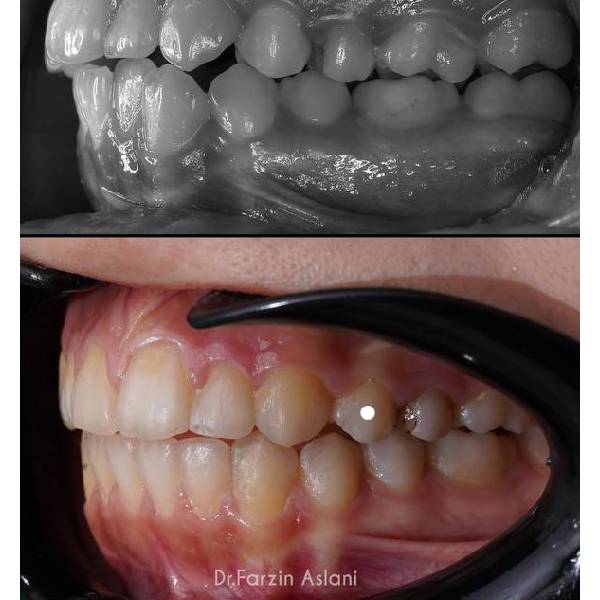

نمونه کار متخصص ارتودنسی تهران

در بخش زیر نمونه کار قبل و بعد ارتودنسی توسط دکتر فرزین اصلانی را مشاهده می کنید :